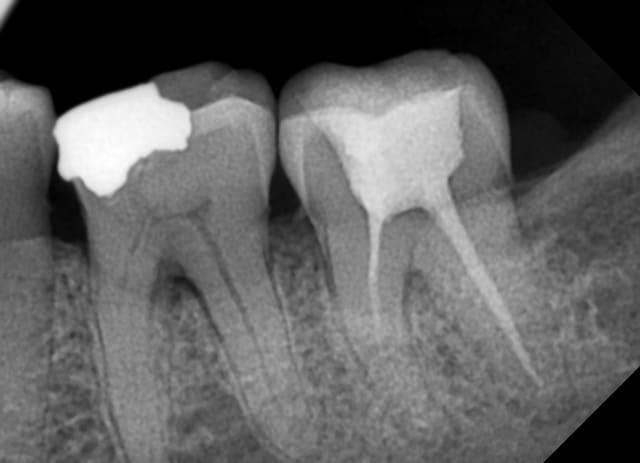

Patient se présente 2 mois avant la pose d'une prothèse totale de genou. Aucun problème ressenti au niveau de ses dents, le suivi a été régulier chez son dentiste.

Que pensez vous de ces dents (le sondage est à la hauteur de ce qu'on voit sur les radios: poches entre 3 et 8 mm sur ces dents)? L'atteinte des furcations est-elle suffisante pour justifier des extracs, ou vous tenteriez de la chir paro pour rétablir tout ça, quitte à déplacer l'intervention orthopédique?

Parce que des atteintes de furcation de stade 1 à 3 comme ici représentent, me semble-t-il, un état altéré des dents et des gencives, susceptibles de se transformer en état inflammatoire aigu (infecté) d'un jour à l'autre.

Et quand tu as une prothèse articulaire, ses surfaces peuvent être colonisées par les bactéries buccales qui entreraient dans le système lors d'un tel état. On peut observer alors un descellement de ces prothèses ou une infection à leur niveau, ce qui nécessite une réintervention.